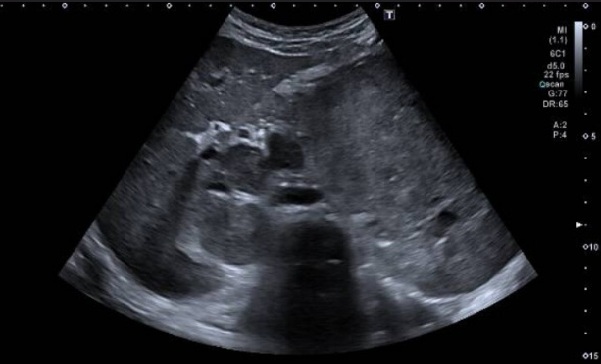

2. ECOGRAFÍA CERVICAL

Ecografía cervical: Lóbulo tiroideo izquierdo aumentado de tamaño a expensas de

imagen nodular sólida, heterogénea, predominantemente isoecoica, sin calcificaciones

y con vascularización desorganizada al examen Doppler color.